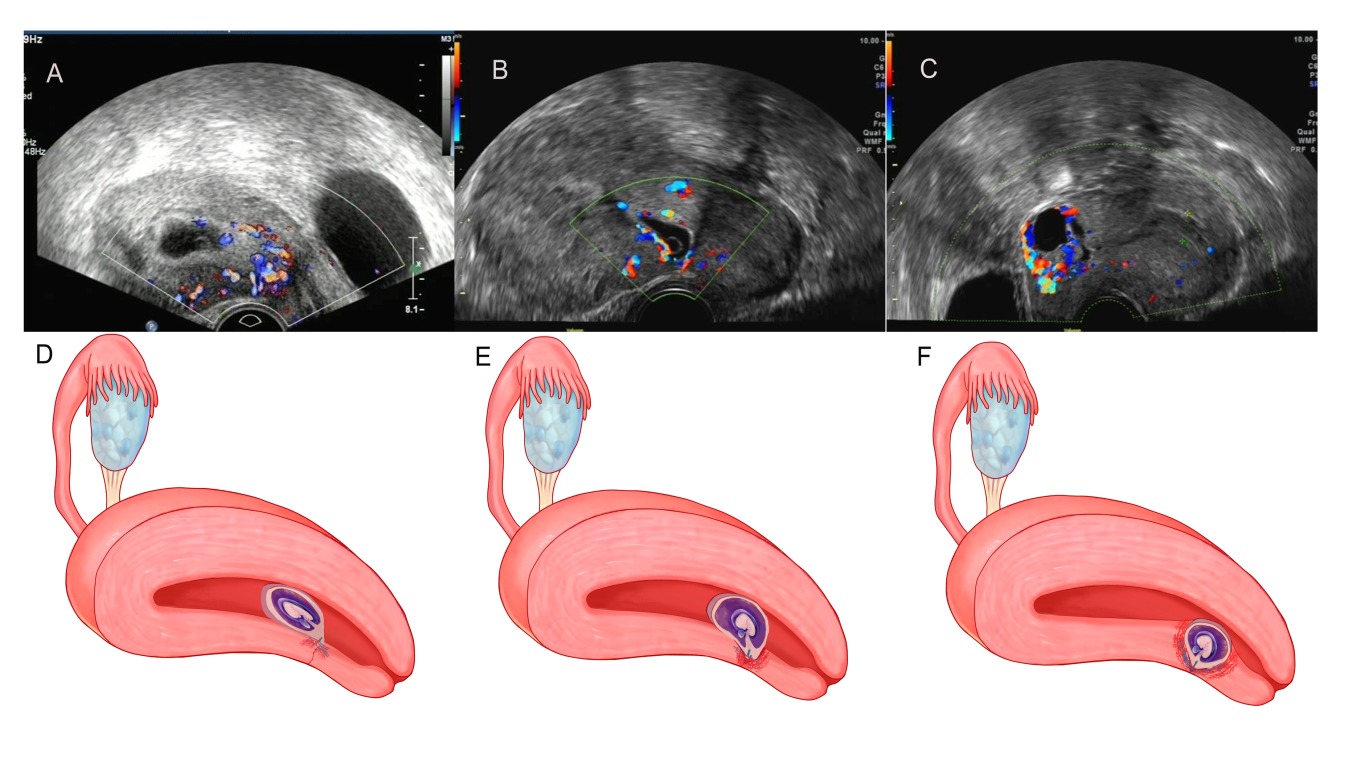

剖宫产瘢痕妊娠的精确评估 与个体化治疗